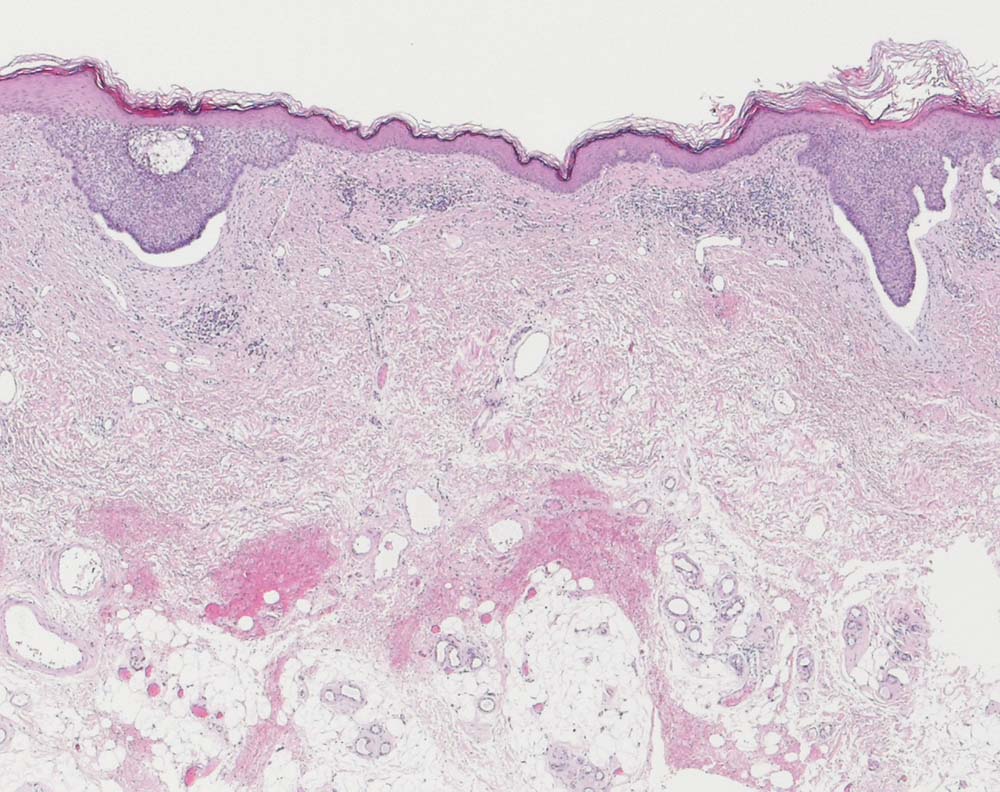

Oberflächlich multizentrisches Basalzellkarzinom

Von der Epidermis ausgehende basaloide Zellnester mit peripherer Palisadierung und charakteristischem Retraktionsartefakt zwischen Tumorzellen und angrenzendem Stroma. Zwischen beiden Zellnestern ist die Haut tumorfrei.

Basaliom Axilla.